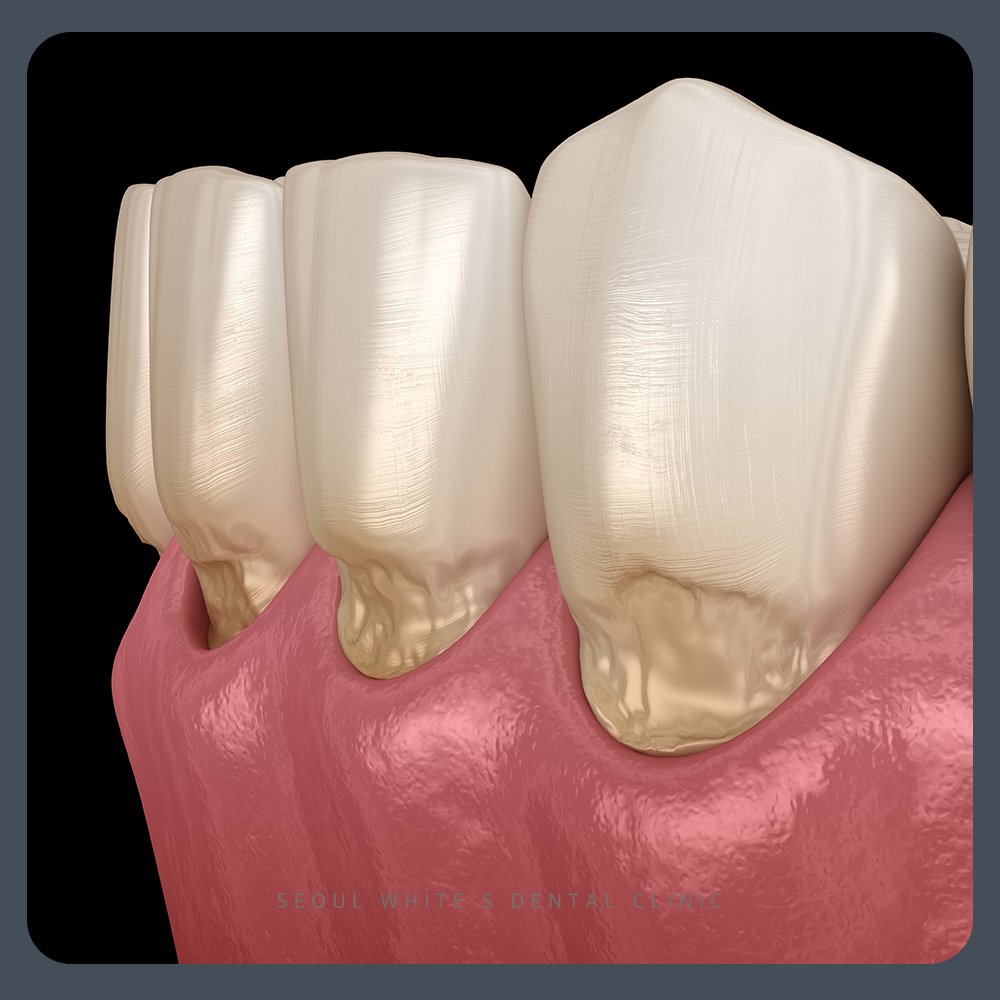

‘치경부 마모증(cervical abrasion)’이란 치아 머리의 뿌리 방향 잇몸경계부위의 ‘치경부’라는 부분이 마모되어 치질의 결손이 발생하는 질환을 의미합니다.

그밖에도 부정교합이나 나이 듦에 따라 누적된 마모로 인해 치아에 마모가 생길 수 있습니다. 치경부 마모증은 마모된 정도에 따라 치료가 달라지는데요.

초기에는 잇솔질 방법을 변경하고 시린이 전용 치악을 사용을 말씀드리며, 치료보다 생활습관을 먼저 바꾸시는 것을 추천드립니다. 좀 더 깊게 진행된 경우에는 마모된 부분을 메우는 치료를 진행하는데요. 레진(resin), 글레스아이오노머(GI)와 같은 재료로 충전할 수 있어요.

만약, V형 마모가 깊고 시림과 통증이 심한 경우는 신경치료를 진행하거나 보철물(crwon)을 해야할 수 있으며, 파절되어 내원하시는 분도 계시므로 이러한 치경부 마모증의 증상이 보이신다면 빠르게 서울화이트S치과에서 진료를 받아보시길 바랍니다.